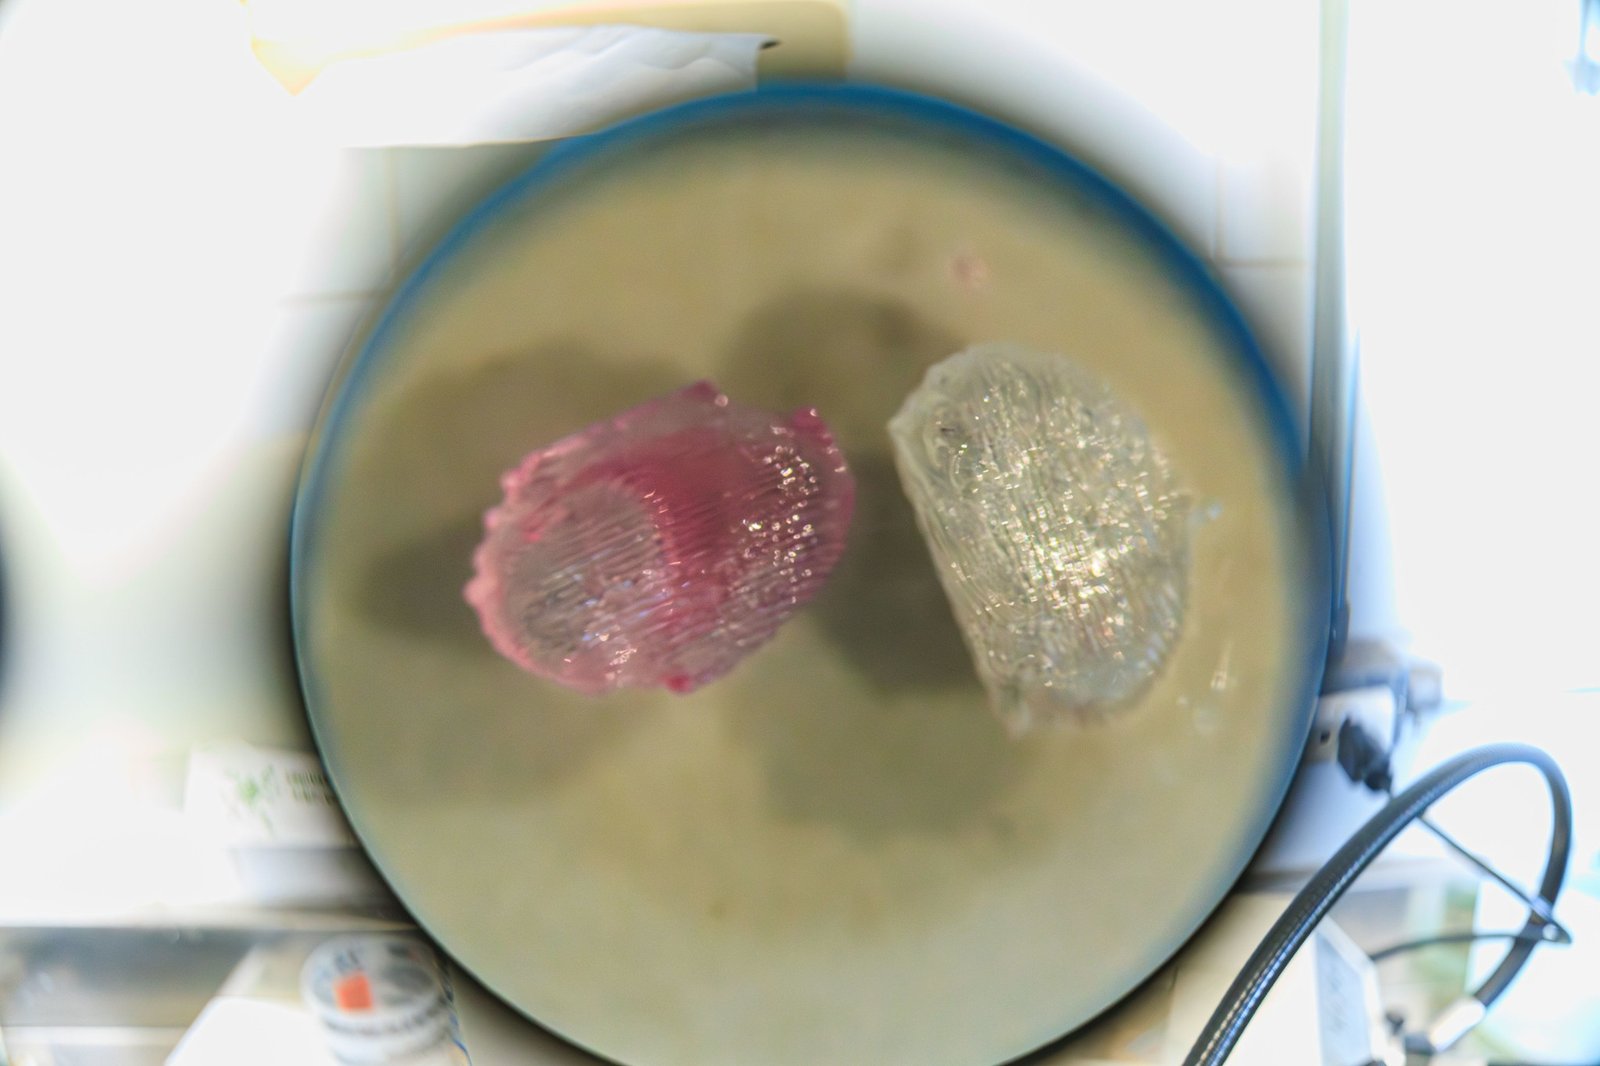

Dispositivo 3D imita ambiente da medula óssea em laboratório

Igor Alisson/Inova Unicamp

A partir daí, desenvolveram o dispositivo em 3D, feito de um material compatível com o corpo humano. Ele funciona como uma estrutura onde as células ficam organizadas e conseguem se manter vivas e funcionando.